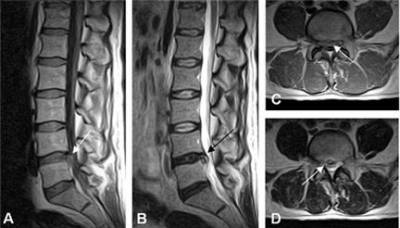

Субхондральный склероз выявляют при проведении рентгенографии и томографии

Субхондральный склероз позвоночника

Утолщение костной ткани позвонков наблюдается при остеохондрозе в области, которая непосредственно соприкасается с поврежденным межпозвонковым диском.

Проявления субхондрального склероза позвоночника зависят от локализации (шейный, грудной или поясничный), степени поражения тканей позвоночника и наличия осложнений (межпозвоночная грыжа, сужение позвоночного канала, защемление нервных корешков и др.).

Больные жалуются на хронические боли в шее и спине. Время от времени возникают обострения с острым болевым синдромом. На более поздних стадиях возникают неврологические осложнения, деформации позвоночного столба, что может стать причиной потери работоспособности и инвалидности.

МРТ позвоночника позволит не только установить факт остеосклероза, но и найти его причину

Основная опасность склероза позвонков заключается в повышении риска спонтанных компрессионных переломов, которые могут возникать даже при минимальных физических нагрузках. Поэтому необходимо как можно раньше выявить проблему и сделать все возможное для предотвращения ее прогрессирования и развития осложнений.